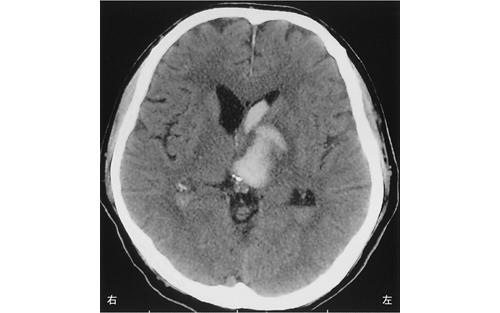

脳梗塞の発生部位によって出現する症状は異なります。この問題では、それぞれの部位における症状を正確に理解することが求められています。

Broca領域は運動性失語の症状が現れる部位であり、遂行機能障害は前頭葉で見られるため、この選択肢は誤りです。

右内包後脚では、左上下肢の運動麻痺が見られるため、この選択肢は正しいです。